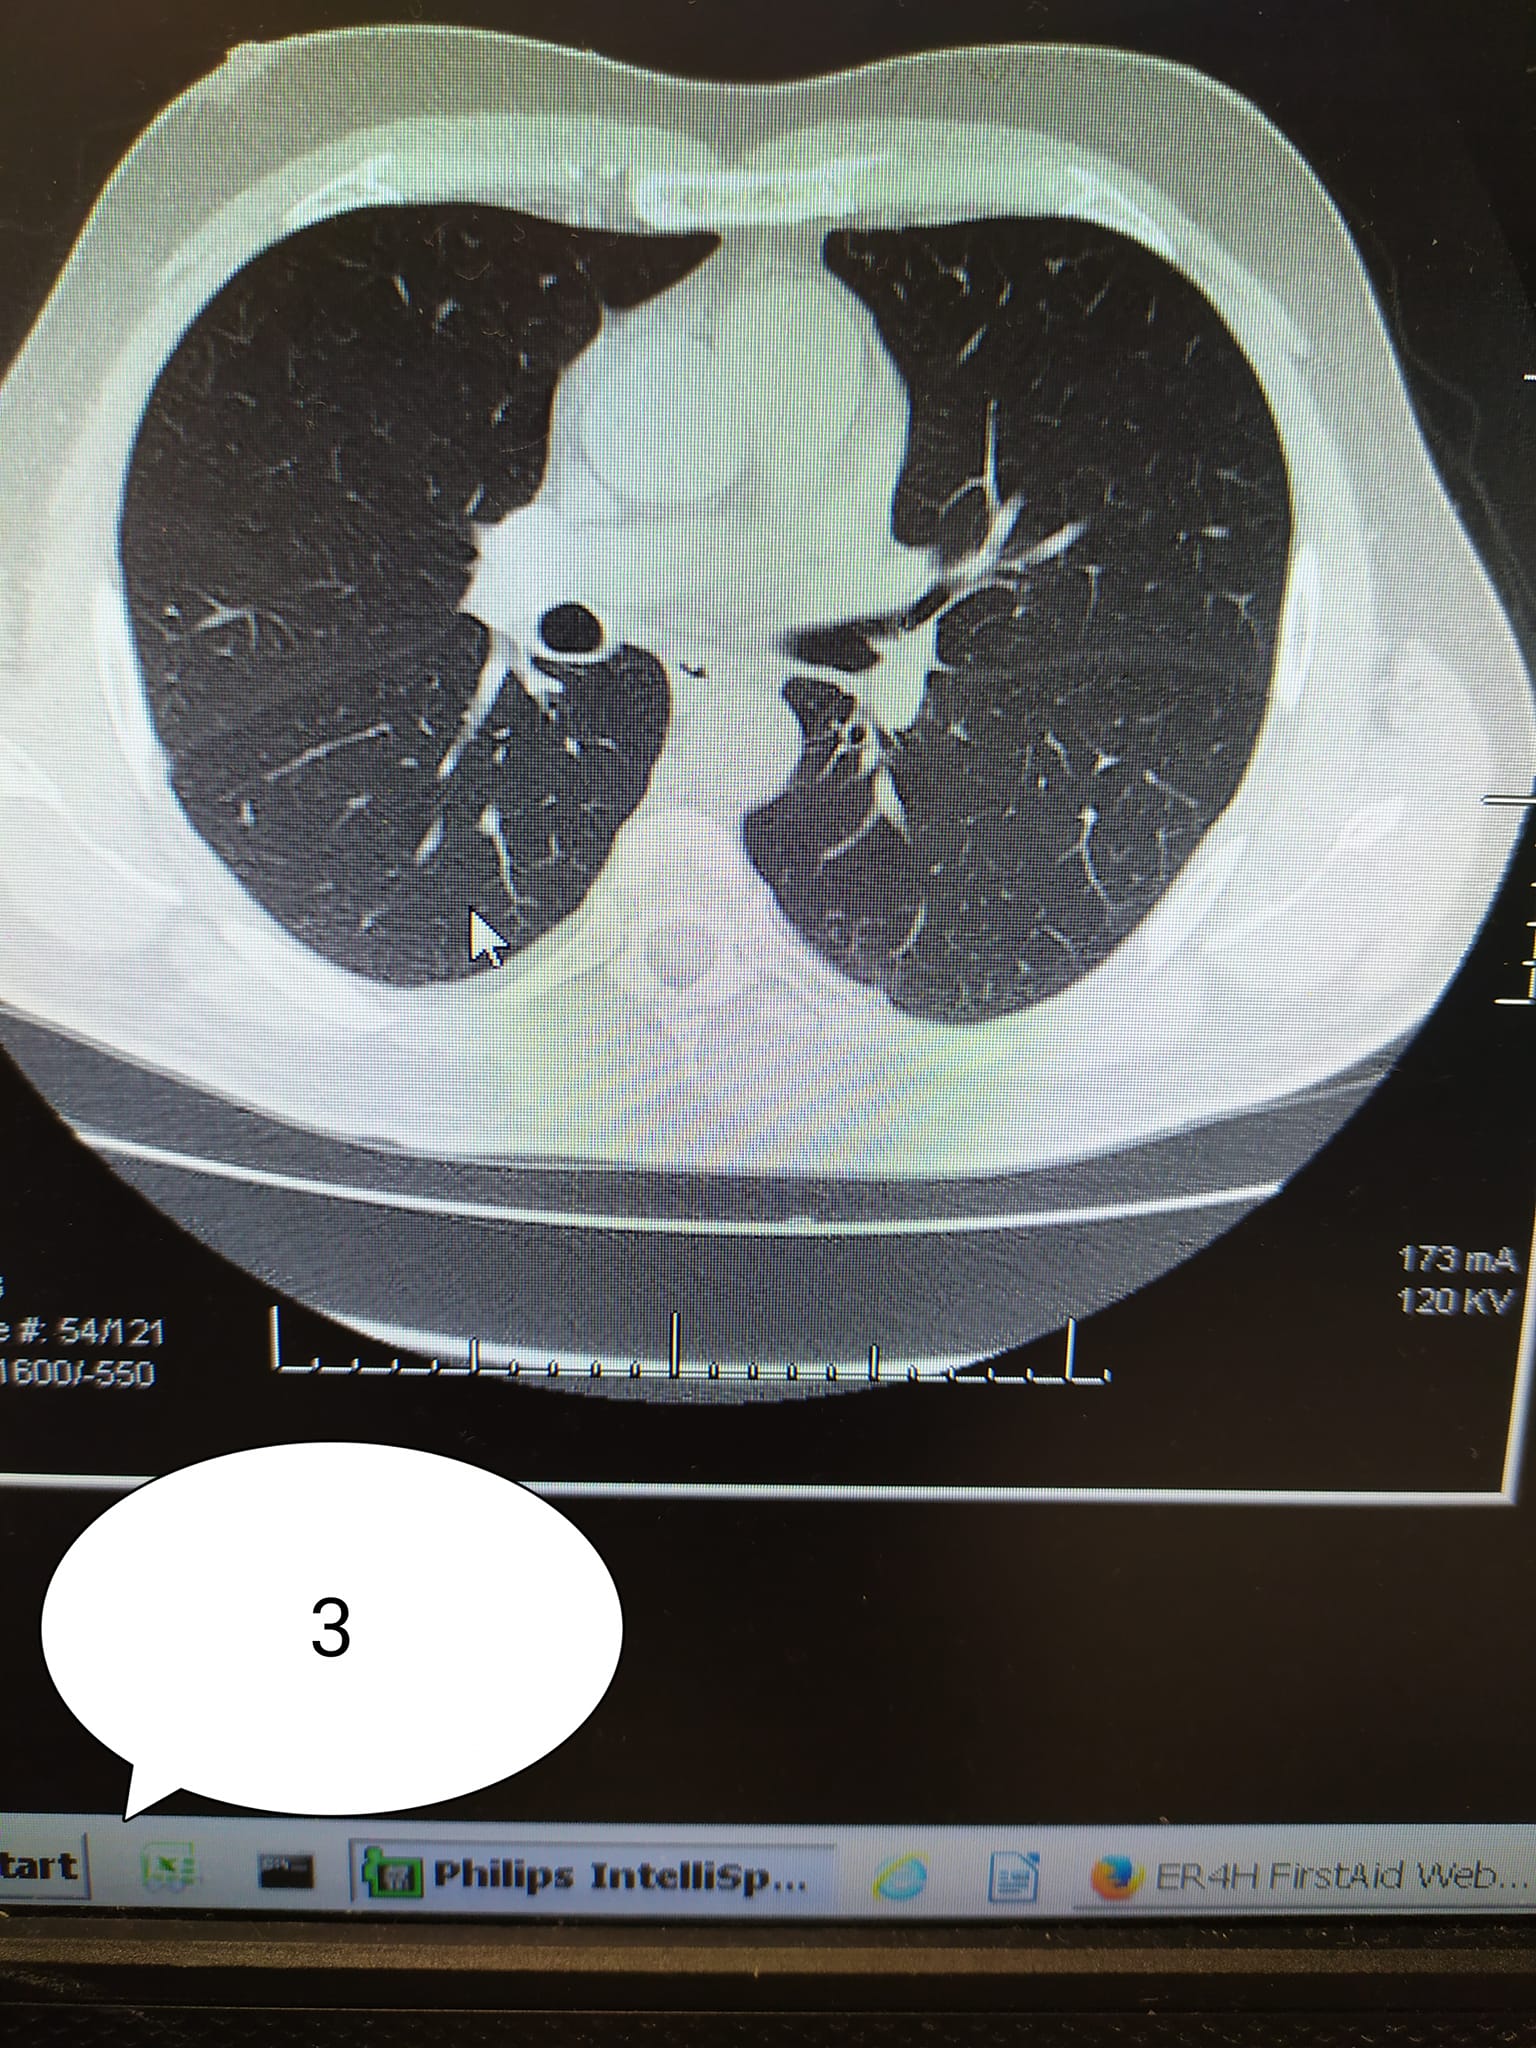

Galmozzi ha poi pubblicato 3 immagini di TC:

3) soggetto di 54 anni FRAGILE per severe copatologie VACCINATO

“Se in 1) e 2) il carico di malattia polmonare è elevato in 1 (circa 60%) e discreto in 2) (circa 35%). Nel soggetto 3) (fragile e con malattie importanti in anamnesi), la malattia non c’è. I primi due ricoverati e con ossigeno, il terzo a casa sua”.